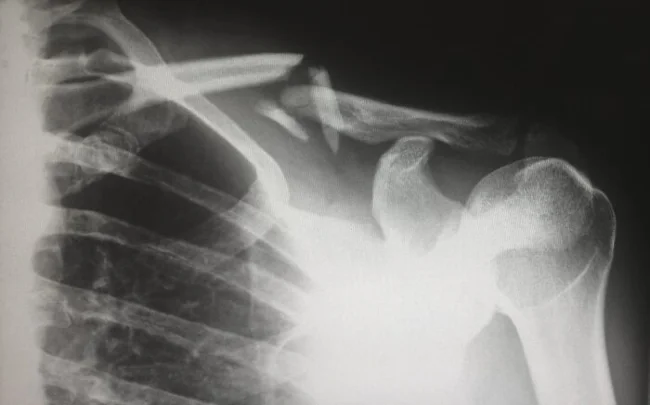

"Когда рентгенография только стала широко доступна для педиатров, они стали замечать огромное количество переломов. Озадаченные врачи предположили, что обнаружили ранее неизвестное заболевание костей у детей. Оказалось, что люди просто не подозревали, насколько распространено жестокое обращение с детьми".